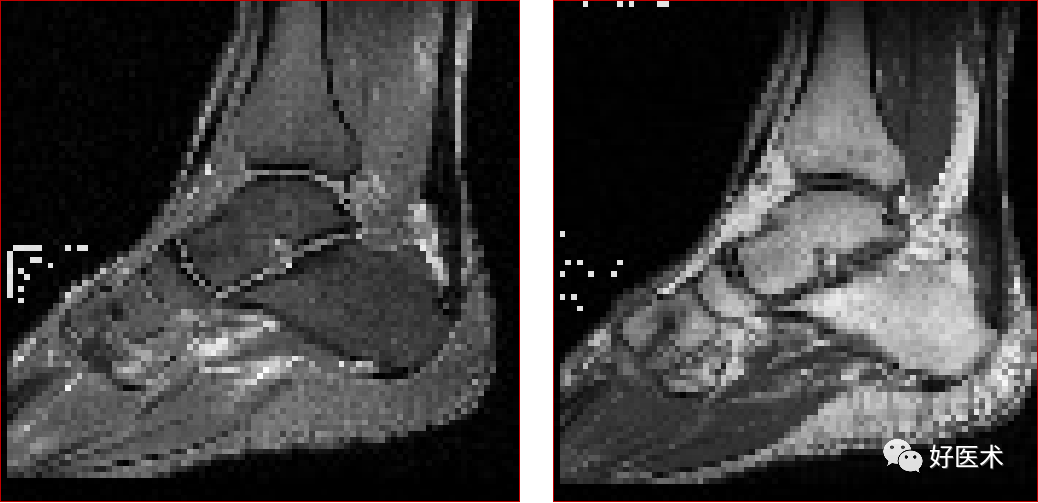

跟腱部分(完全)撕裂:跟腱最厚处前后径一般小于6mm,在踝关节上方2 – 6cm处跟腱纤维交叉走行,血液供应减少,易撕裂

慢性跟腱炎

慢性跟腱炎并跟腱部分撕裂

跟腱撕裂